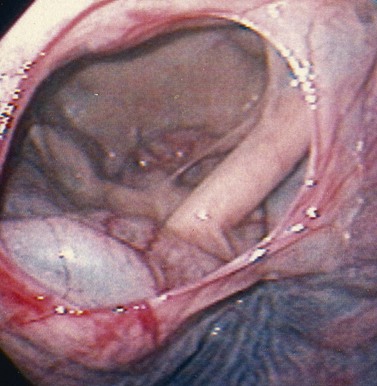

image

Fig. 19.19 The bulla of the ventral conchal sinus is seen protruding into the caudal maxillary sinus beneath the rostral margin of the frontomaxillary aperture. The bulla structure is sometimes obscured by the caudal portion of the floor of the dorsal conchal sinus.